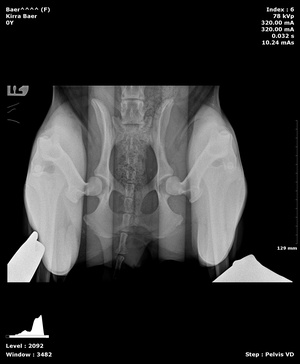

Pennhip X-rays in Williamsfield & Elmwood, IL

Wags and Whiskers is one of the few facilities in the state that offers PennHip diagnostics. PennHipp is a tool used to measure hip laxity. It can detect the presence of osteoarthritis or hip dysplasia in canine companions. Breeders often use this service to determine breeding soundness. It can be performed on patients as young as 16 weeks old.